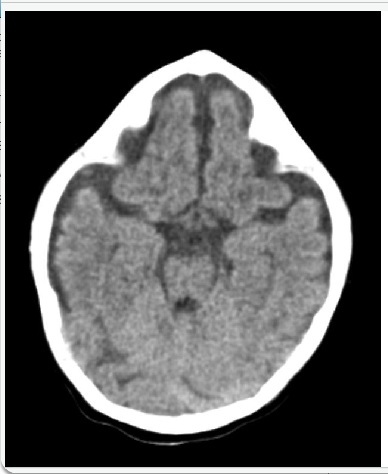

Hasil CT Scan aksial kepala tanpa kontras pada neonatus yang terlihat pada gambar menunjukkan kelainan deformitas yang disebut :

D. Siantosis Metopic

Metopic synostosis also known as Trigonocephaly is caused by premature fusion of the metopic suture. Normally metopic sutures close at 3-9 months of age. Premature fusion can lead to the observed wedge shaped deformity in the cranial vault. There is a resulting restriction of growth in the bilateral frontal bones with compensatory growth in the parietal bones. The deformity can be most easily appreciated above the nasion and extends from the glabella to the anterior fontanelle. Trigonocephaly accounts for approximately 5% of all craniosynostoses and is thought to result from abnormal signaling in growth factors including transforming growth factor (TGF) and fibroblast growth factor (FGF).

Unicoronal synostosis is characterized by flattening of the forehead on the affected side with contralateral bossing which is not present in this CT. This along with the foreshortening of the orbit and zygoma produces the harlequin eye. Sagittal synostosis is also a straightforward diagnosis where the CT shows the characteristic long-boat shaped head along with narrowing of the biparietal diameter. For lambdoid synostosis, the ipsilateral tragus and petrous bone are drawn posteriorly and the midline of the foramen magnum is drawn to the affected side. Bicoronal synostosis is characterized by a very broad and tall forehead from the premature fusion of both sutures with characteristic CT findings. Metopic synostosis and other cranial synostoses may lead to increased intracranial pressure if left untreated as well as other neurocognitive deficits and behavioral abnormalities.